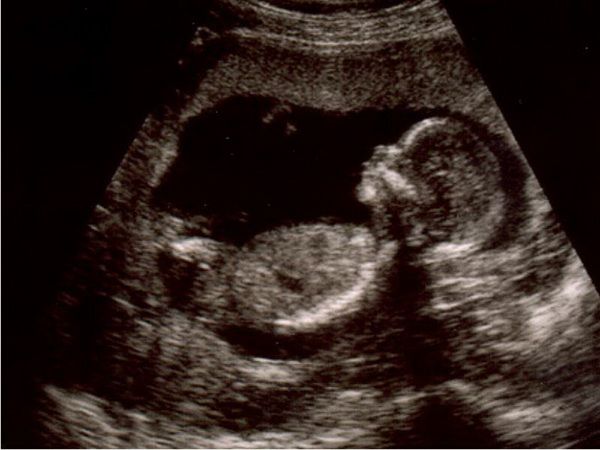

Як розвивається малюк? До цього терміну зріст і вагу дитини порівнянні з плодом авокадо і становлять 10,8 – 12 см і 80 – 115 р. При проходженні процедури УЗД на даному терміні, лікар виробляє виміри довжини і обхвату окремих частин тіла. Голова в 14 тижнів має окружність в 11 – 13 див. Пуповина, яка забезпечує харчування малюка має діаметр дорівнює 2 см, а її довжина становить близько 50 див.

Особливості поведінки дітей при багатоплідній вагітності

Розмір живота при багатоплідній вагітності на цьому терміні ще несуттєво відрізняється від габаритів вагітної з однією дитиною. Місця в матці поки ще досить для обох дітей. При двійні зростання кожного з малюків орієнтовно становить 11 см, а важить кожен з них не більше 100 р.

Головною особливістю багатоплідної вагітності на цьому терміні, є тісне спілкування малюків один з одним. Та оскільки в цей період активно розвивається хапальний рефлекс, діти намагаються вхопитися одне за одного.